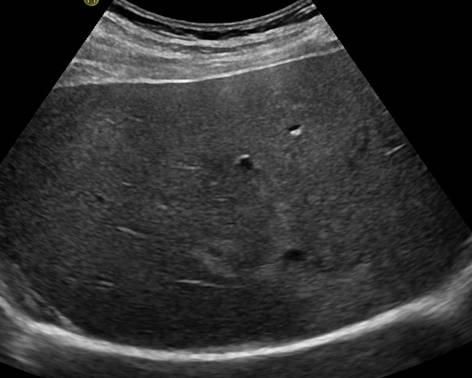

Gan nhiễm mỡ - Ảnh 2

Gan nhiễm mỡ

» Thông tin: Nam giới – 42 tuổi.

» Lâm sàng: Kiểm tra sức khỏe.